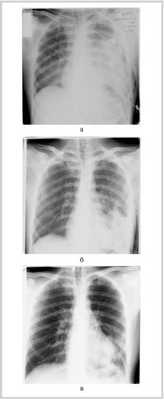

У 31 (19,9%) из 156 пострадавших (в том числе у 5 с легочным кровотечением) при рентгенографии в 1-е сутки после травмы патологических изменений легочной ткани не было выявлено. У 28 (17,9%) пострадавших оценить состояние легких при первом исследовании не представлялось возможным из-за значительного пневмоторакса и/или гемоторакса, что потребовало срочного дренирования плевральной полости и повторного исследования. Патологические изменения легочных полей были обнаружены у 125 пострадавших, однако имелись неточности в интерпретации результатов исследования. Так, негомогенное затенение легочного поля выявлено у 86 (55,1%) пациентов, что расценивалось как ушиб или гематома легкого (рис. 1, а), Рисунок 1. Рентгенограммы пациента после закрытой травмы груди. а — 1-е сутки: негомогенное затенение левого легочного поля за счет ушиба; б — 10-е сутки: положительная динамика в виде повышения прозрачности верхних и средних отделов левого легочного поля. На фоне сохраняющегося затенения нижней доли левого легкого определяются две полости с горизонтальным уровнем жидкости; в — 30-е сутки: положительная динамика — усиление прозрачности легочного поля, уменьшение размеров полостей в легком при одновременном исчезновении газового компонента. в том числе у 28 пострадавших эти изменения дифференцировать от гидроторакса не представлялось возможным. В 17 (10,9%) наблюдениях снижение прозрачности легких было расценено как интерстициальный отек или гиповентиляция, у 13 (8,3%) - как пневмония. Лишь в 2 наблюдениях были выявлены тонкостенные полости с газом и жидкостью в легком на фоне некоторого снижения прозрачности легочного поля, все остальные наблюдения травматических газосодержащих легочных полостей в течение первых 3-4 сут, по данным рентгенологического исследования, остались незамеченными из-за сопутствующего ушиба ткани легкого. В одном наблюдении гематома нижней доли правого легкого была расценена как расширение тени сердца.

Положительная динамика рентгенологической картины при легочных кровоизлияниях характеризовалась снижением интенсивности затенения легочных полей начиная с 3-5-х суток после травмы. На этом фоне в указанные сроки в 29 наблюдениях выявлены ранее не определявшиеся очаговые, интенсивные, округлой формы тени с четкими контурами, в том числе в 7 наблюдениях - с горизонтальным уровнем жидкости (рис. 1, б). При сравнении с данными СКТ из указанных 29 наблюдений газовые включения в гематоме легкого имелись в 11. В динамике во всех этих наблюдениях отмечалась тенденция к уменьшению размеров гематомы при одновременном снижении интенсивности затенения (рис. 1, в). Полости, заполненные только газом, по данным рентгенологического метода визуализировались только в 3 наблюдениях.